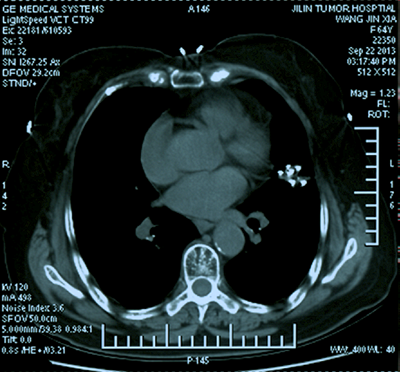

吉林省腫瘤醫(yī)院介入中心建筑面積2200平方米,開放床位35張。擁有UNIQ FD20C 血管造影機?,F(xiàn)有主任醫(yī)師1名,副主任醫(yī)師1名,主治醫(yī)師2名,醫(yī)師2名。(其中博士1名,碩士4名)??剖易?992年開展腫瘤介入微創(chuàng)的診療工作,30年以來,開展了肝癌、肺癌、肝轉(zhuǎn)移癌、肺轉(zhuǎn)移癌、膽管癌、消化道腫瘤、泌尿系統(tǒng)腫瘤、骨轉(zhuǎn)移瘤、盆腔腫瘤等各種良、惡性腫瘤的微創(chuàng)介入手術(shù)2萬余例(包括腫瘤動脈灌注化療栓塞術(shù)、微波消融術(shù)和125I放射粒子植入術(shù)(病種包括:肝癌、肝轉(zhuǎn)移癌、肺癌、肺轉(zhuǎn)移癌、骨轉(zhuǎn)移癌、腎上腺轉(zhuǎn)移癌等)、子宮肌瘤及肌腺癥栓塞術(shù)、經(jīng)皮穿刺骨水泥注射椎體成形術(shù)、食管、膽管狹窄支架置入術(shù)、各部位腫瘤急性出血的栓塞止血術(shù)、胃腸營養(yǎng)管、腸梗阻導(dǎo)管植入術(shù)等)。在國內(nèi)外首先提出低功率消融的治療理念,經(jīng)過1000余例臨床手術(shù)證實,療效確切,無并發(fā)癥,得到了國內(nèi)外同行的廣泛認(rèn)可,并在全國逐步推廣。2011年在國內(nèi)外率先開展三氧化二砷聯(lián)合局部微創(chuàng)介入治療中晚期肝癌的隨機對照研究,提出了早期全身干預(yù)與局部治療的序貫療法,取得了明顯的成績,經(jīng)過中位60個月隨訪期,治療組明顯優(yōu)于常規(guī)對照組,中晚期肝癌的5年生存期達到38.2%,達到了國際領(lǐng)先水平。在國內(nèi)率先開展了多項靶向藥及免疫治療聯(lián)合介入微創(chuàng)治療肝癌、肺癌等臨床研究,取得了較好的成績。在科研方面,共發(fā)表SCI及核心期刊論文100余篇;2019年度獲吉林省科技進步二等獎1項,吉林省科技進步三等獎1項,2014年獲長春市科技進步二等獎1項??剖覟榧质】拱﹨f(xié)會介入治療專業(yè)委員會主委單位,主辦國家級及省級學(xué)術(shù)會議10余次。

(肺癌的介入治療)(盆腔惡性腫瘤的介入治療)

(腦腫瘤的介入治療)(子宮肌瘤的介入治療)